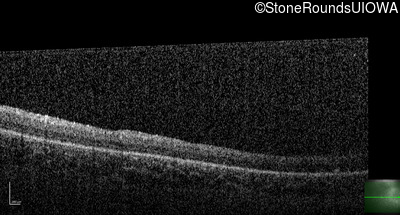

Optical Coherence Tomography - Left - No Light Perception

Exemplar / OCT Stack